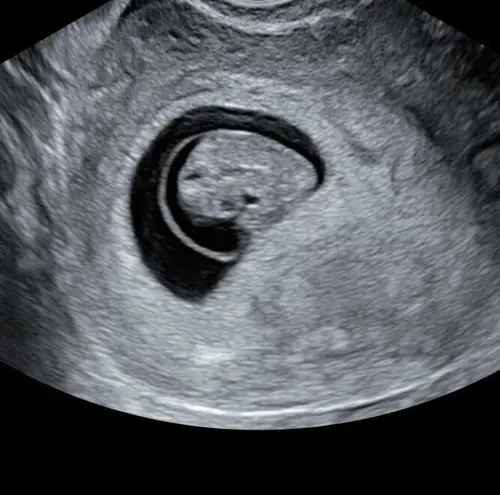

Afgelopen maandag ongeveer 8 weken ❤️ van kruin tot stuit 1,6cm